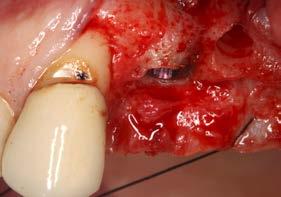

Explantación atraumática y recambio de implantes mal posicionados y afectados por periimplantitis sumado a la utilización de implantes estrechos y cortos. Enfoque mínimamente invasivo de un caso de atrofia ósea moderada

42 | INVESTIGACIÓN CLÍNICA